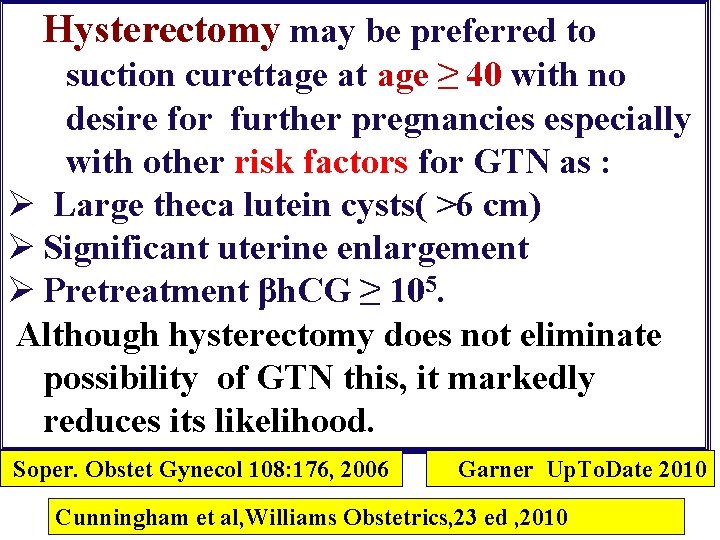

Hysterectomy may be preferred to suction curettage at age ≥ 40 with no desire for further pregnancies especially with other risk factors for GTN as : Ø Large theca lutein cysts( >6 cm) Ø Significant uterine enlargement Ø Pretreatment βh. CG ≥ 105. Although hysterectomy does not eliminate possibility of GTN this, it markedly reduces its likelihood. Soper. Obstet Gynecol 108: 176, 2006 Garner Up. To. Date 2010 Cunningham et al, Williams Obstetrics, 23 ed , 2010